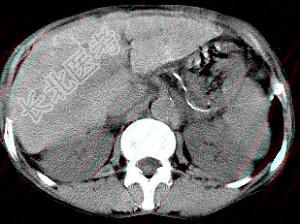

- 单项选择题男,40岁有血吸虫感染史, 腹胀不适,食欲减退, CT扫描所见如图,最可能的诊断是 ( )

A、肝炎后肝硬化

B、血吸虫后肝硬化

C、酒精性肝硬化

D、胆汁性肝硬化

E、脂肪肝